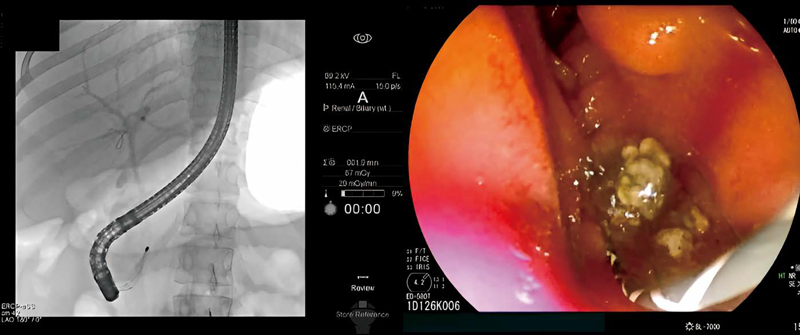

담관 담석은 증상이 없어도 치료한다. 급성담관염, 급성췌장염, 폐쇄성 황달 같은 합병증 위험이 크기 때문이다. 담관 담석은 내시경적 역행성 담췌관조영술(ERCP)로 즉시 제거하는 것이 치료 원칙이다. ERCP는 내시경과 방사선을 이용한 치료법이다. 이경주 교수는 “내시경을 십이지장까지 삽입한 상태에서 담관에 조영제(영상을 잘 보기 위해 사용하는 약품)를 주입해 X선으로 담석의 정확한 위치를 확인한다. 이후 미리 넣어둔 가이드선을 따라 바스켓이나 풍선 기구를 담관에 넣어 담석을 제거한다. 담낭 담석이 동반된 경우에는 복강경 수술로 담낭도 제거한다. 이는 담낭에서 넘어와 유발되는 총담관 담석의 재발을 방지하기 위한 것”이라고 설명했다.

ERCP 시술을 통해 담관 담석을 제거하는 모습 ⓒ한림대동탄성심병원